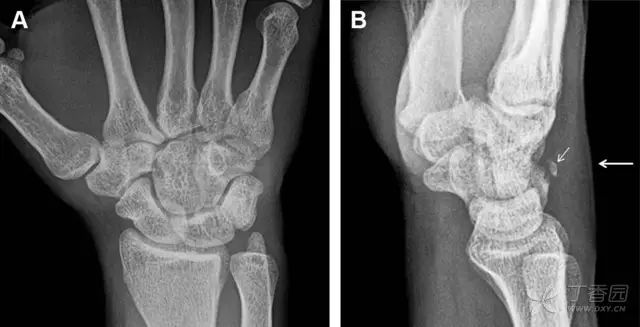

常规进行前后位、侧位、斜位 X 线检查,对于大多数桡骨远端骨折来说不容易漏诊;但是对于无移位的骨折,特别是桡骨茎突骨折,容易漏诊。桡骨茎突骨折是一斜行的骨折,常累及关节面,常发生于轴向应力或直接打击。

图 1 57 岁女性,摔倒后手掌撑地,桡骨茎突压痛。(A~C)前后位、斜位、侧位片示软组织肿胀(*)和发丝样骨折(白色箭头);(D~F)2 周后,前后位、斜位、侧位片示骨折线显明,由于新骨痂沉积而呈现透亮线与硬化线并存;(G~I)另一患者,桡骨茎突骨折在前后位及侧位片上显示不明显,而在斜位片显示更清楚

舟状骨骨折 60%~70% 发生于腰部,15% 发生于近极, 10% 发生于远极, 8% 发生于远端关节面。除了常规的前后位、侧位、斜位片外,还需要拍专门的舟状骨位片(腕关节尺偏,以舟状骨为中心的腕关节前后位片),特别是鼻烟壶有压痛时。

图 2 舟状骨骨折 (A、B)第 1 例患者,舟状骨远极关节内骨折(白色箭头),斜位片显示较清楚(B);(C、D)第 2 例患者,舟状骨腰部骨折(虚线箭头),斜位片显示较清楚(D);(E~H)第 3 例患者,舟状骨近极骨折,常规 X 线片均未看到骨折,而在舟状骨位片上才能见到骨折(虚线圆)